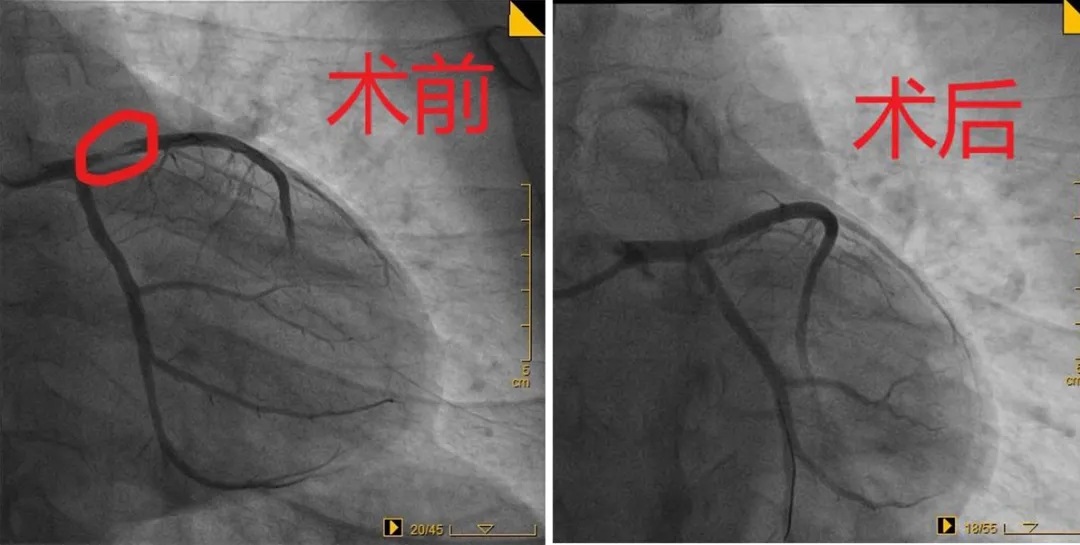

2020年12月14日,36岁的王先生因胸痛3天来我院就诊,诊断为急性冠脉综合症,急诊冠脉造影显示心脏左前降支近段狭窄80%。

该患者IVUS检查显示狭窄部位由斑块破裂引起,高希春主任、巩海英副主任为患者进行了冠状动脉药物球囊置入术。这样既解决了患者血管狭窄的问题,也没有放置金属支架,不需要长期服用抗凝药物,远期预后良好,患者非常满意。

血管狭窄70%就要放心脏支架? 高希春主任介绍:“冠脉造影显示血管狭窄70%以上的患者,如果症状不明显,我们建议进一步血管内超声检查。这项检查在冠脉造影的基础上,不仅能清晰显示血管壁的厚度、管腔面积、形状,还可以精准评估冠脉内斑块大小、性质,以及支架贴壁情况、膨胀情况等。因对冠状动脉内病变看的更仔细,因此被形象的称为透视冠状动脉的‘第三只眼睛’。如果是血管夹层引起的狭窄,不管狭窄程度多少,我们都建议进行支架治疗,如果是斑块破裂引起的狭窄,根据患者的情况可以进行药物球囊置入术,无需放支架。” 对于年轻患者、不愿置入金属支架的患者,药物球囊是最佳的选择。我院心内科目前已独立开展急诊冠状动脉药物球囊置入术50多例,均取得了良好的效果。